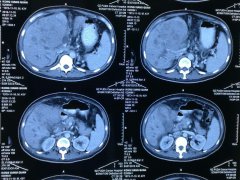

张禾教授在苏州国医堂为粉丝讲课中